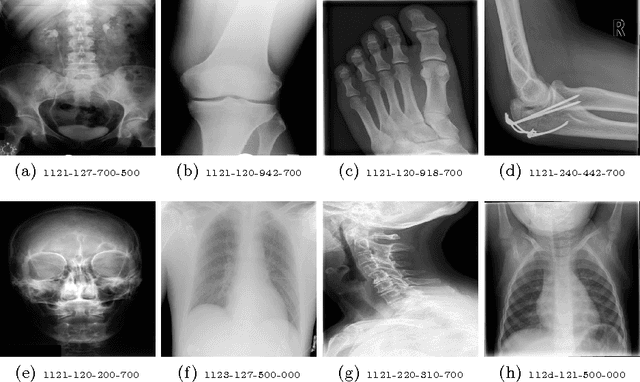

Medical images can be a valuable resource for reliable information to support medical diagnosis. However, the large volume of medical images makes it challenging to retrieve relevant information given a particular scenario. To solve this challenge, content-based image retrieval (CBIR) attempts to characterize images (or image regions) with invariant content information in order to facilitate image search. This work presents a feature extraction technique for medical images using stacked autoencoders, which encode images to binary vectors. The technique is applied to the IRMA dataset, a collection of 14,410 x-ray images in order to demonstrate the ability of autoencoders to retrieve similar x-rays given test queries. Using IRMA dataset as a benchmark, it was found that stacked autoencoders gave excellent results with a retrieval error of 376 for 1,733 test images with a compression of 74.61%.